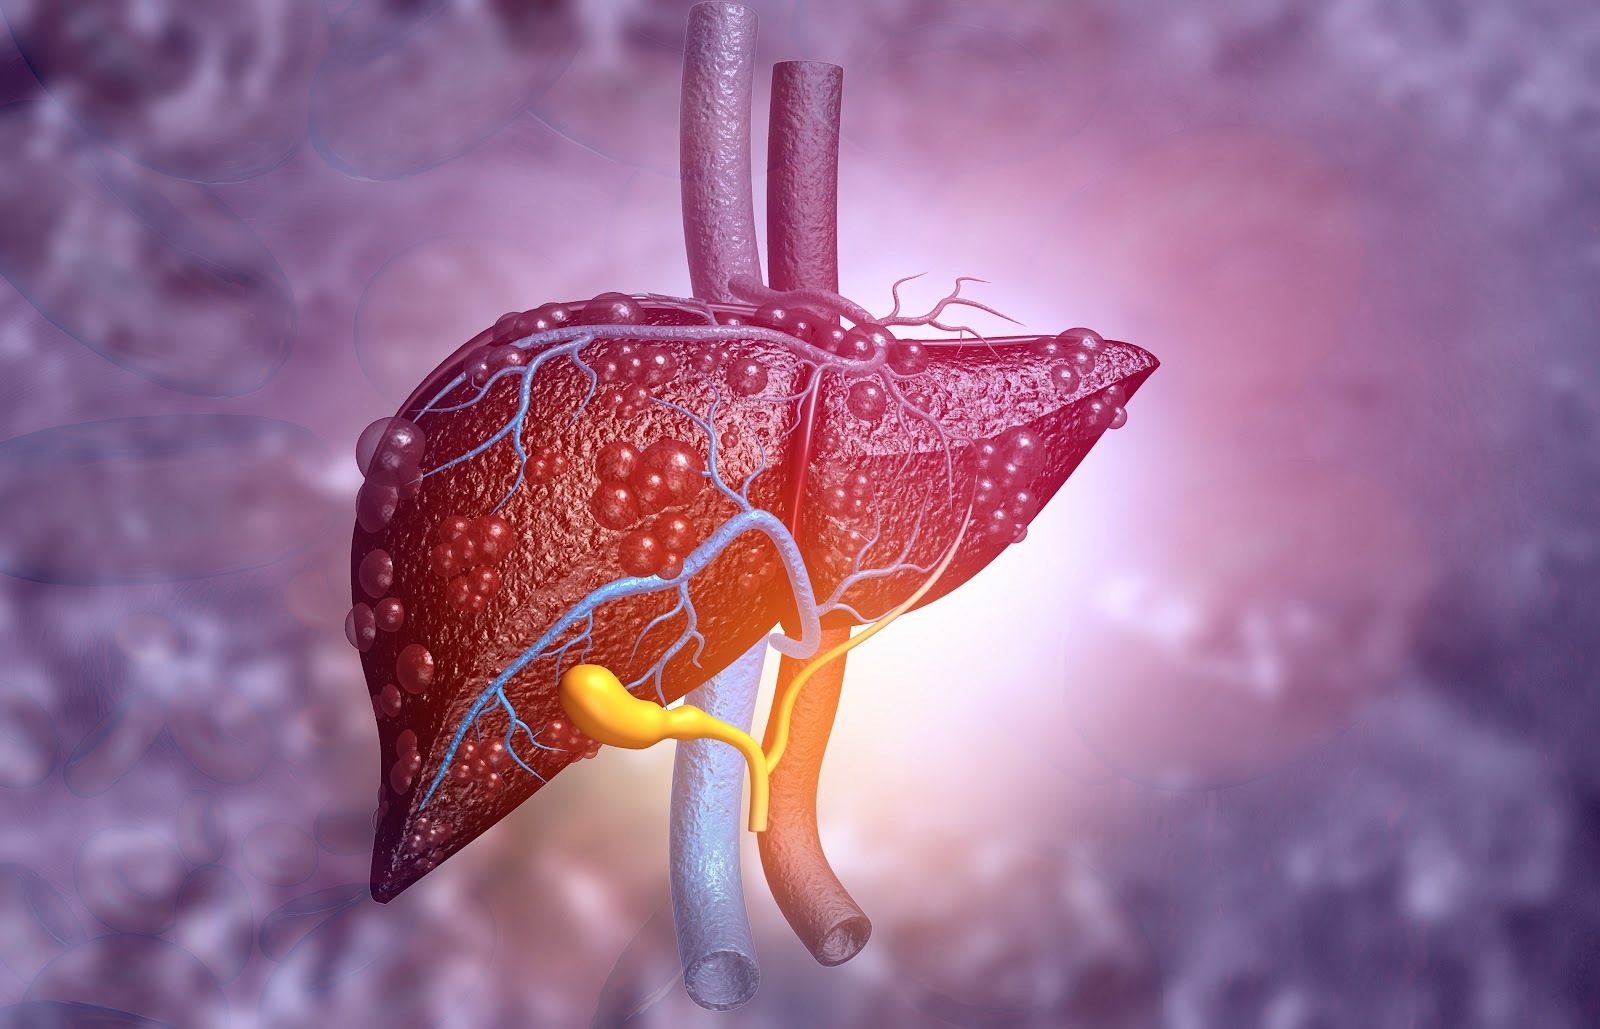

Bei der Leber (Hepar) handelt es sich um die größte Drüse im menschlichen Körper. Die rotbraune Drüse erreicht ein Gewicht von 1,4 bis 2 kg. Im rechten Oberbauch wird sie von den unteren Rippen geschützt. Anatomisch gliedert sich das Organ in einen linken und einen rechten Leberlappen, wobei der linke Lappen wesentlich größer ist. Die Leber ist mit mehreren Bändern in der Bauchhöhle verankert. Unten an der Leber befindet sich die Leberpforte (Porta hepatis). Hier treten Blutgefäße, Nervenfasern, Gallengänge und Lymphgefäße in das Organ ein. Im Inneren zeigt sich die Leber als mehrlappiges System, welches wiederum aus vielen kleinen Leberläppchen und Leberzellen (Hepatozyten) besteht.

Die Leberarterie und die Pfortader, welche sich an der Unterseite der Leber befinden, treten über die Leberpforte in das Organ ein. Über die Leberarterie fließt sauerstoffreiches Blut in die Leber. Zeitgleich fließt über die Pfortader sauerstoffarmes Blut in die Leber. Bei der Pfortader handelt es sich um eine Vene, die das Blut aus dem Bauchraum (Milz, Bauchspeicheldrüse, Magen, Darm, Gallenblase) in die Leber leitet. In der Folge gelangen so verschiedenste Stoffe in die Leberzellen. Hierzu zählen unter anderem Einfachzucker und Aminosäuren. Nun entscheidet die Leber je nach Bedarf und Qualität, welche Stoffe direkt benötigt, gespeichert oder umgewandelt werden. Nicht umsonst ist die das Organ unter dem Namen „Chemiewerk“ bekannt.

Die Leber ist eng mit der Gallenblase verknüpft und die Zusammenarbeit ist für unsere Verdauung und Vitaminverwertung von großer Bedeutung. Aus der anatomischen Perspektive befindet sich die Gallenblase unter dem Organ in einer kleinen Einbuchtung und ist über einen Gallengang direkt mit ihr verbunden. Pro Tag stellt die Leber in etwa 600 ml bis 1.000 ml Gallenflüssigkeit her. Die Gallenblasse speichert das gelb-bräunliche Sekret und verdickt dieses. Bei der Verdauung von fettreichem Essen gibt die Gallenblase die Gallenflüssigkeit an den Darm und Zwölffingerdarm ab. Hier werden wiederum Fette aus der Nahrung gespalten und verarbeitet.